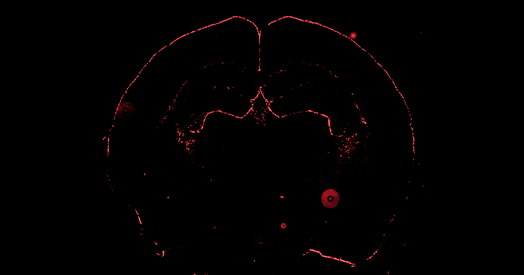

Investigadores están poniendo el foco en los astrocitos, unas células cerebrales que antes se creían solo de 'soporte'. Ahora se sabe que son clave para el desarrollo de las conexiones neuronales y regulan comportamientos como la ansiedad y las interacciones sociales. Estudios recientes en ratones muestran cómo estas células influyen en la respuesta emocional, la acción de la oxitocina e incluso en la memoria.

Los astrocitos, lejos de ser pasivos, se comunican entre sí formando redes extensas que abarcan grandes áreas del cerebro, permitiendo una comunicación a larga distancia. Se ha descubierto que secretan proteínas que podrían afectar el crecimiento de las neuronas, lo cual se investiga como un posible factor en síndromes relacionados con el autismo. Estos hallazgos sugieren que los astrocitos podrían ser objetivos terapéuticos para futuras intervenciones.